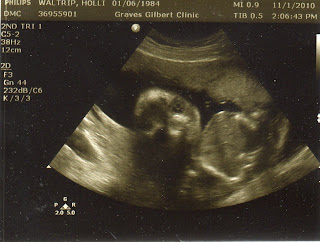

Because of this, my doctor scheduled me to have another ultrasound yesterday (at my 24 week appointment) to try to get a view of the things we couldn't see last time. It took about 10 seconds for the lady to say something like "Well, the baby just doesn't want me to see what I need to see." She said he was sitting with his bottom down, looking face forward AGAIN. As soon as she turned the screen around, this is what we saw...

Looks very familiar don't you think?  Needless to say, I was very excited when she and my doctor told me we get to have ANOTHER ultrasound at my 28 week appointment!  He wants to try again to get those shots that he hasn't been able to get yet.  I was trying to figure it up today, and I think we've gotten to have a total of 9 ultrasounds so far.  Don't get me wrong, I am definitely not complaining.  We love seeing our little guy every few weeks, and I've decided he just likes having his picture taken.  :)

One of the neatest things about this ultrasound was that I got to see him blinking.  (Brad wasn't able to see it.)  It was the weirdest thing!  The lady captured this picture just as he was blinking.  I'm pretty sure his eyes are closed in this one...

We also got to see his nostrils, lips (of course he was moving his mouth...eating I guess), and his boy parts.